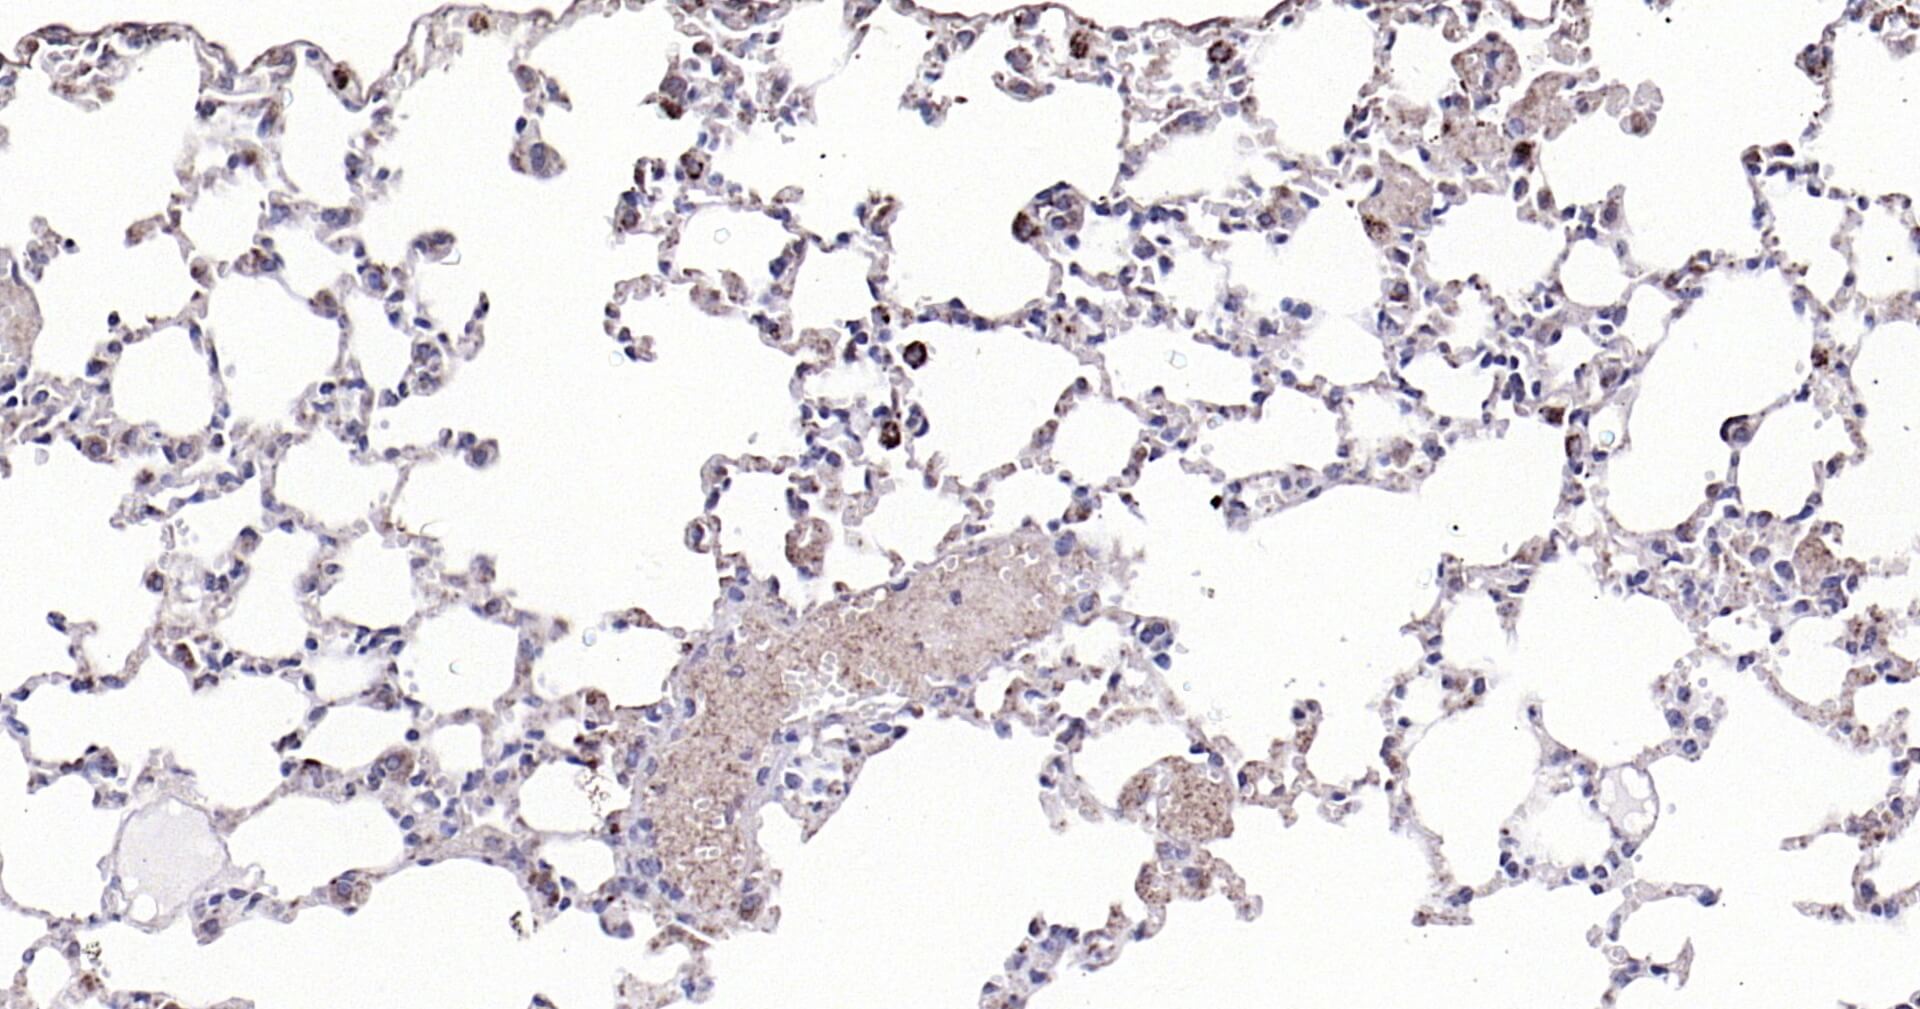

Immunohistochemical analysis of paraffin embedded mouse lung tissue slide using IHC0124M (Mouse Cathepsin L IHC Kit).

描述 IHC0124M is a ready-to-use IHC kit for staining of mouse Cathepsin L. The kit provides all reagents, from antigen retrieval to cover slip mounting, that require little to no diluting or handling prior to use. Simply apply the reagents to your sample slide according to the protocol and you're steps away from obtaining high-quality IHC data. The protein encoded by this gene is a lysosomal cysteine proteinase that plays a major role in intracellular protein catabolism. Its substrates include collagen and elastin, as well as alpha-1 protease inhibitor, a major controlling element of neutrophil ela